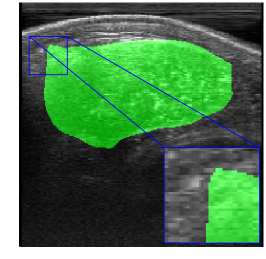

Rib Eye Area (REA). This image dataset consists of ultrasound images of the Longissimus dorsi muscle between the 11th and 13th ribs of cattle. The goal is to automatically calculate the rib eye area (REA), an important region for decision making during cattle breeding. The main challenge is the uncertainty in the REA annotation, since the image is noisy and even experts have difficulty in delimiting the borders of this region. Fig. 3 presents examples of images and the annotation made by a specialist. We can observe that some borders are absent and depend on the subjectivity and knowledge of the annotator. To evaluate the segmentation methods, 76 images with resolution were obtained and labeled by an expert. Due to the number of images, the division of the images in training and testing followed 5-fold cross-validation.

REA dataset. This image dataset has high uncertainty during labeling due to noise from the ultrasound image. In some cases, the border of REA is not completely visible and must be estimated by the specialist. Therefore, the proposed approach becomes essential to obtain accurate segmentation at the edges. The segmentation examples in Fig. 6 show that the baseline was not able to define the REA correctly due to the uncertainty of the labeling. On the other hand, the proposed approach presents results close to the specialist in regions that the border needs to be estimated.